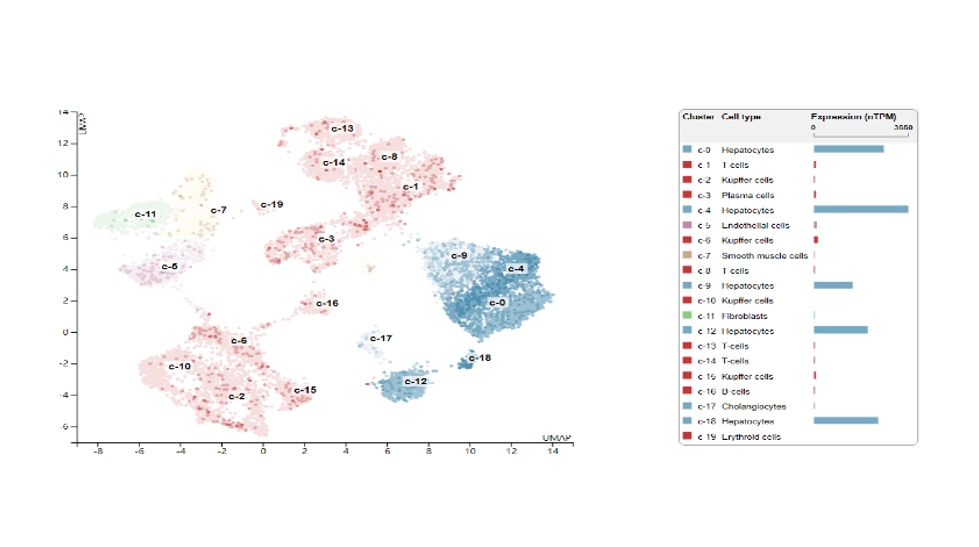

在 Hep3B 细胞中验证表达模式